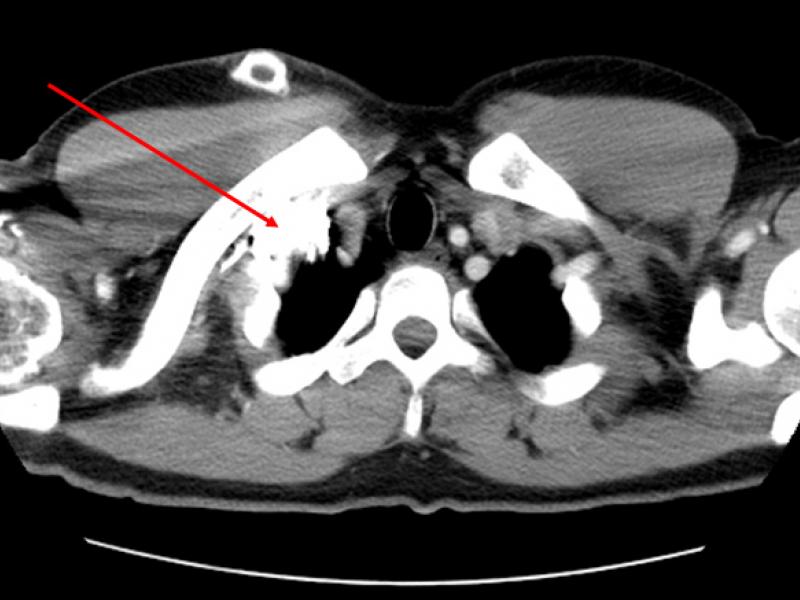

IV Placement to Increase or Decrease Diagnostic Yield of CT Angiography in Penetrating Neck Trauma

November 09 2016

Penetrating neck trauma is a serious cause of morbidity and